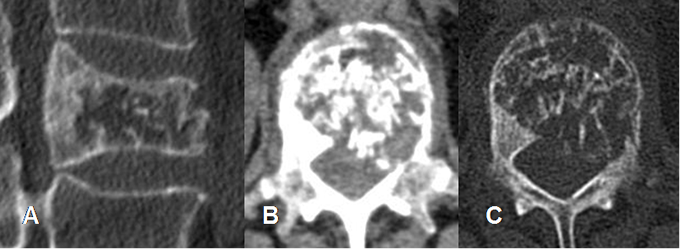

Fig 150. Hemangioma óseo.

A: Rx lateral, B: TAC axial en ventana de tejido y C: en ventana osea. Area radiolúcida con signo de la empalizada, secundario al engrosamiento de la trabeculación vertical y puntos escleróticos rodeados por grasa en el TAC, por hemangioma óseo.

Fig 151. Hemangioma óseo.

A: TAC reconstrucción sagital, B: TAC axial en ventana de tejido y C: en ventana ósea. Fractura patológica de una vértebra lumbar afectada por un hemangioma, con fragmento retropulsado.